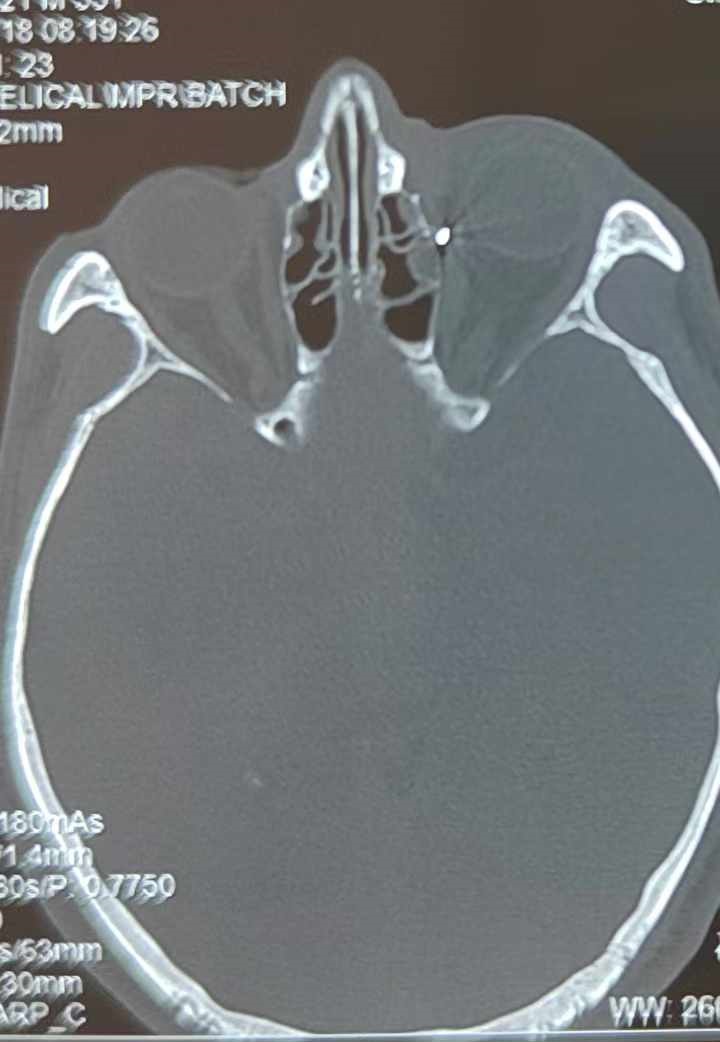

從CT報告中可以看出,高先生眼內(nèi)的異物不是很大,但位于眼窩深處,緊鄰鼻骨,從CT影像判斷應(yīng)該是金屬或合金異物。一般臨床上遇到這樣的情況,醫(yī)生會建議“保守觀察”,若異物傷及神經(jīng)、發(fā)生炎癥感染等,則需到條件較好、有眼眶病和眼外傷專業(yè)醫(yī)師的醫(yī)院進(jìn)行二期眶內(nèi)異物取出術(shù)(2021年《中國眼眶異物診斷和治療專家共識》)。

手術(shù)十分順利,李海波博士設(shè)計好了取出路徑,用這根細(xì)磁棒取出了一個米粒大小的鐵屑,過程中未造成二次傷害和大創(chuàng)面?zhèn)凇Pg(shù)后CT檢查顯示,高先生眼內(nèi)再無異物,他此時才松了一口氣。